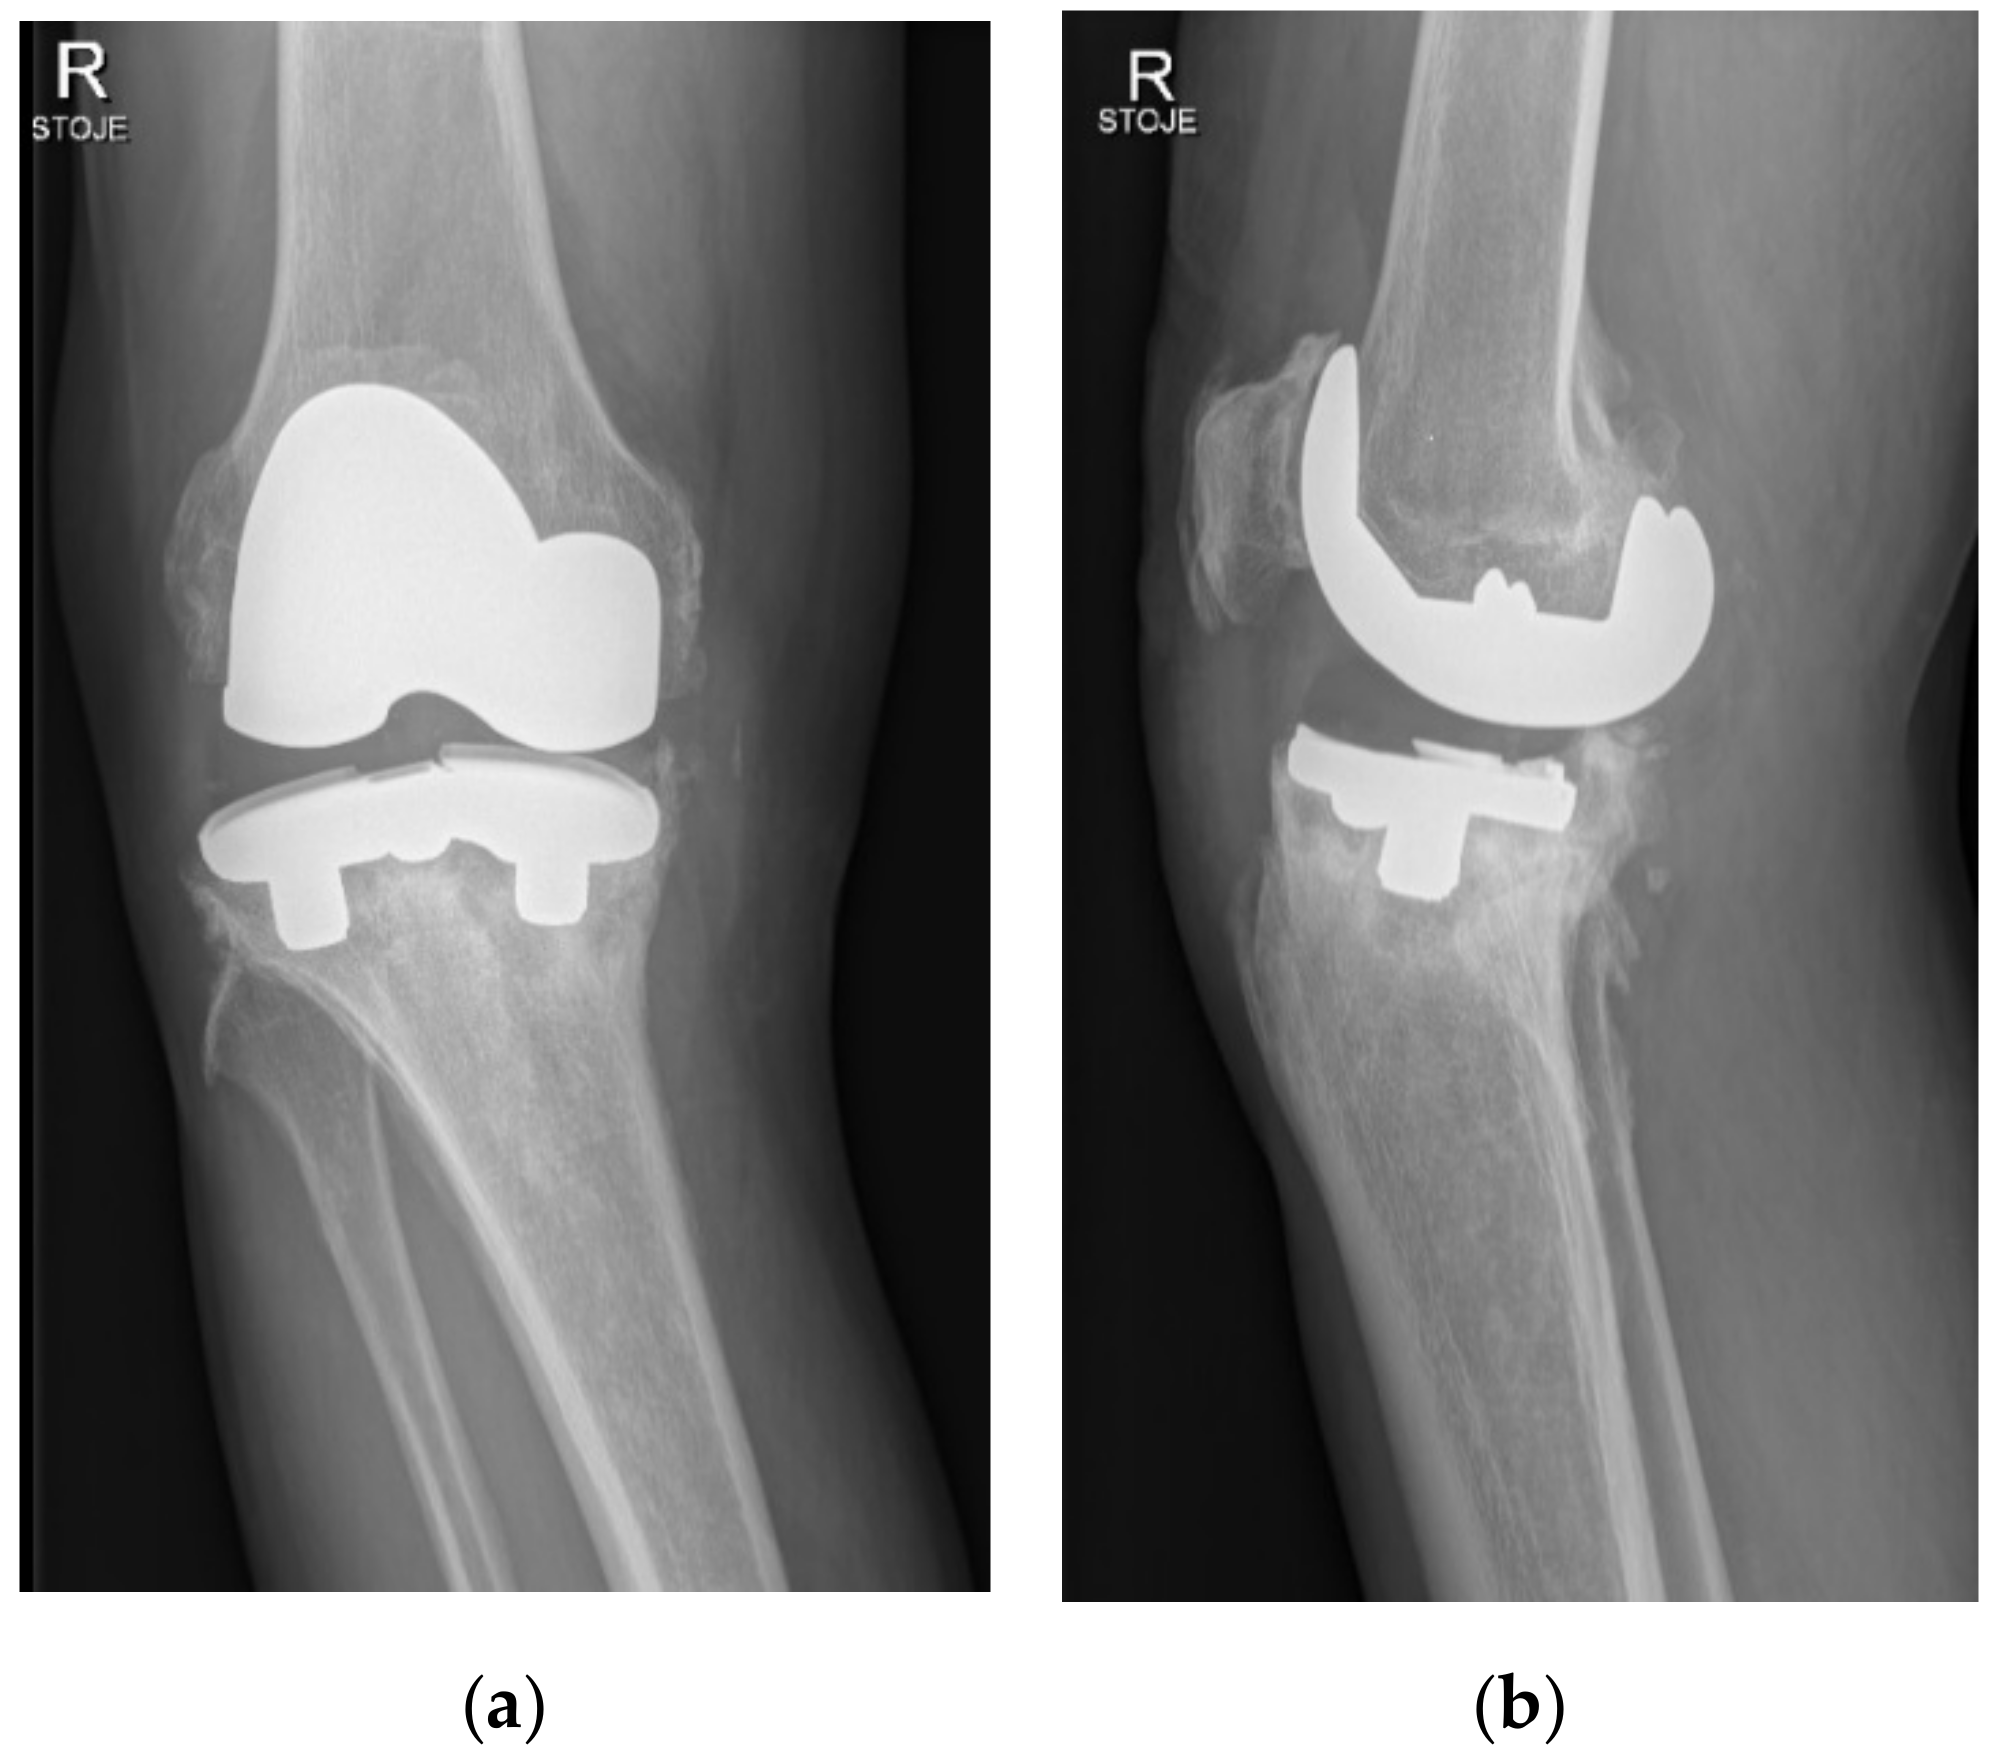

3. Results

The patient was a 64-year-old physically active Caucasian man (weight = 88 kg, body mass index (BMI) = 27.8 kg/m2) with advanced varus right knee OA who had a primary knee replacement through a medial parapatellar approach with a commercially available uncemented system (NexGen©, Trabecular Metal™ LPS-Flex, Zimmer, Inc., Warsaw, IN, USA). The uncemented components were chosen because the bone quality was high, and a particularly dense sclerotic bone was found at the medial tibial plateau (Figure 1). A size E femoral component, a size 5 Trabecular Metal™ modular tibial component, and a 14 mm high shape-moulded UHMWPE posterior stabilised insert was implanted by an experienced arthroplasty surgeon in a tertiary centre (IN). The patient was instructed to walk with crutches for 6 weeks, and full weight bearing was allowed afterwards.

Figure 1. Anteroposterior (a) and lateral (b) radiographs of the right knee on the day of surgery after inserting the total uncemented endoprosthesis with modular porous tantalum tibial tray.